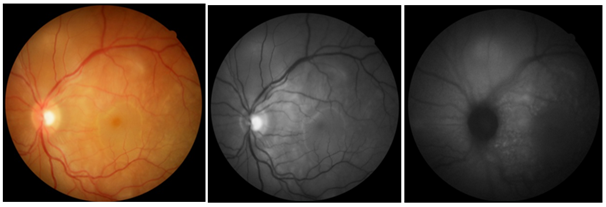

A.E.C.F., 29 years old, male, was seen complaining of low visual acuity in his left eye for 3 days. Patient without comorbidities, did not use routine medication and had no family history of ophthalmic diseases and trauma. In the first evaluation, she presented: visual acuity (without correction) of the right eye (RIGHT EYE): 20/25 and left eye (LEFT EYE): 20/70. In the biomicroscopy of the anterior segment, the right eye was unchanged; left eye with hyperemia of conjunctiva 2 +/4 +, transparent cornea, anterior chamber formed, reaction in anterior chamber 2 +/ 4 +, flare 1 +/ 4 + and posterior synechiae. Intraocular pressure by Goldmann applanation tonometer, RIGHT EYE: 12mmHg, LEFT EYE: 22mmHg. Retinography of the right eye showed a stained optic nerve with physiological excavation, a macula without changes, an applied retina and a healed toxoplasmosis plaque in the temporal retinal region (Figure 1). Laboratory tests were requested, including serology for infectious diseases, and eye drops of prednisolone 1% at 6 / 6h with weekly weaning and tropicamide 1% at 8 / 8h were started in the left eye. The patient returned after 15 days reporting improvement in hyperemia and pain in the left eye, but with worsening visual acuity in both eyes: 20/100 in RE and figures in LE.

Figure 1 Retinography of the right eye in 2018.